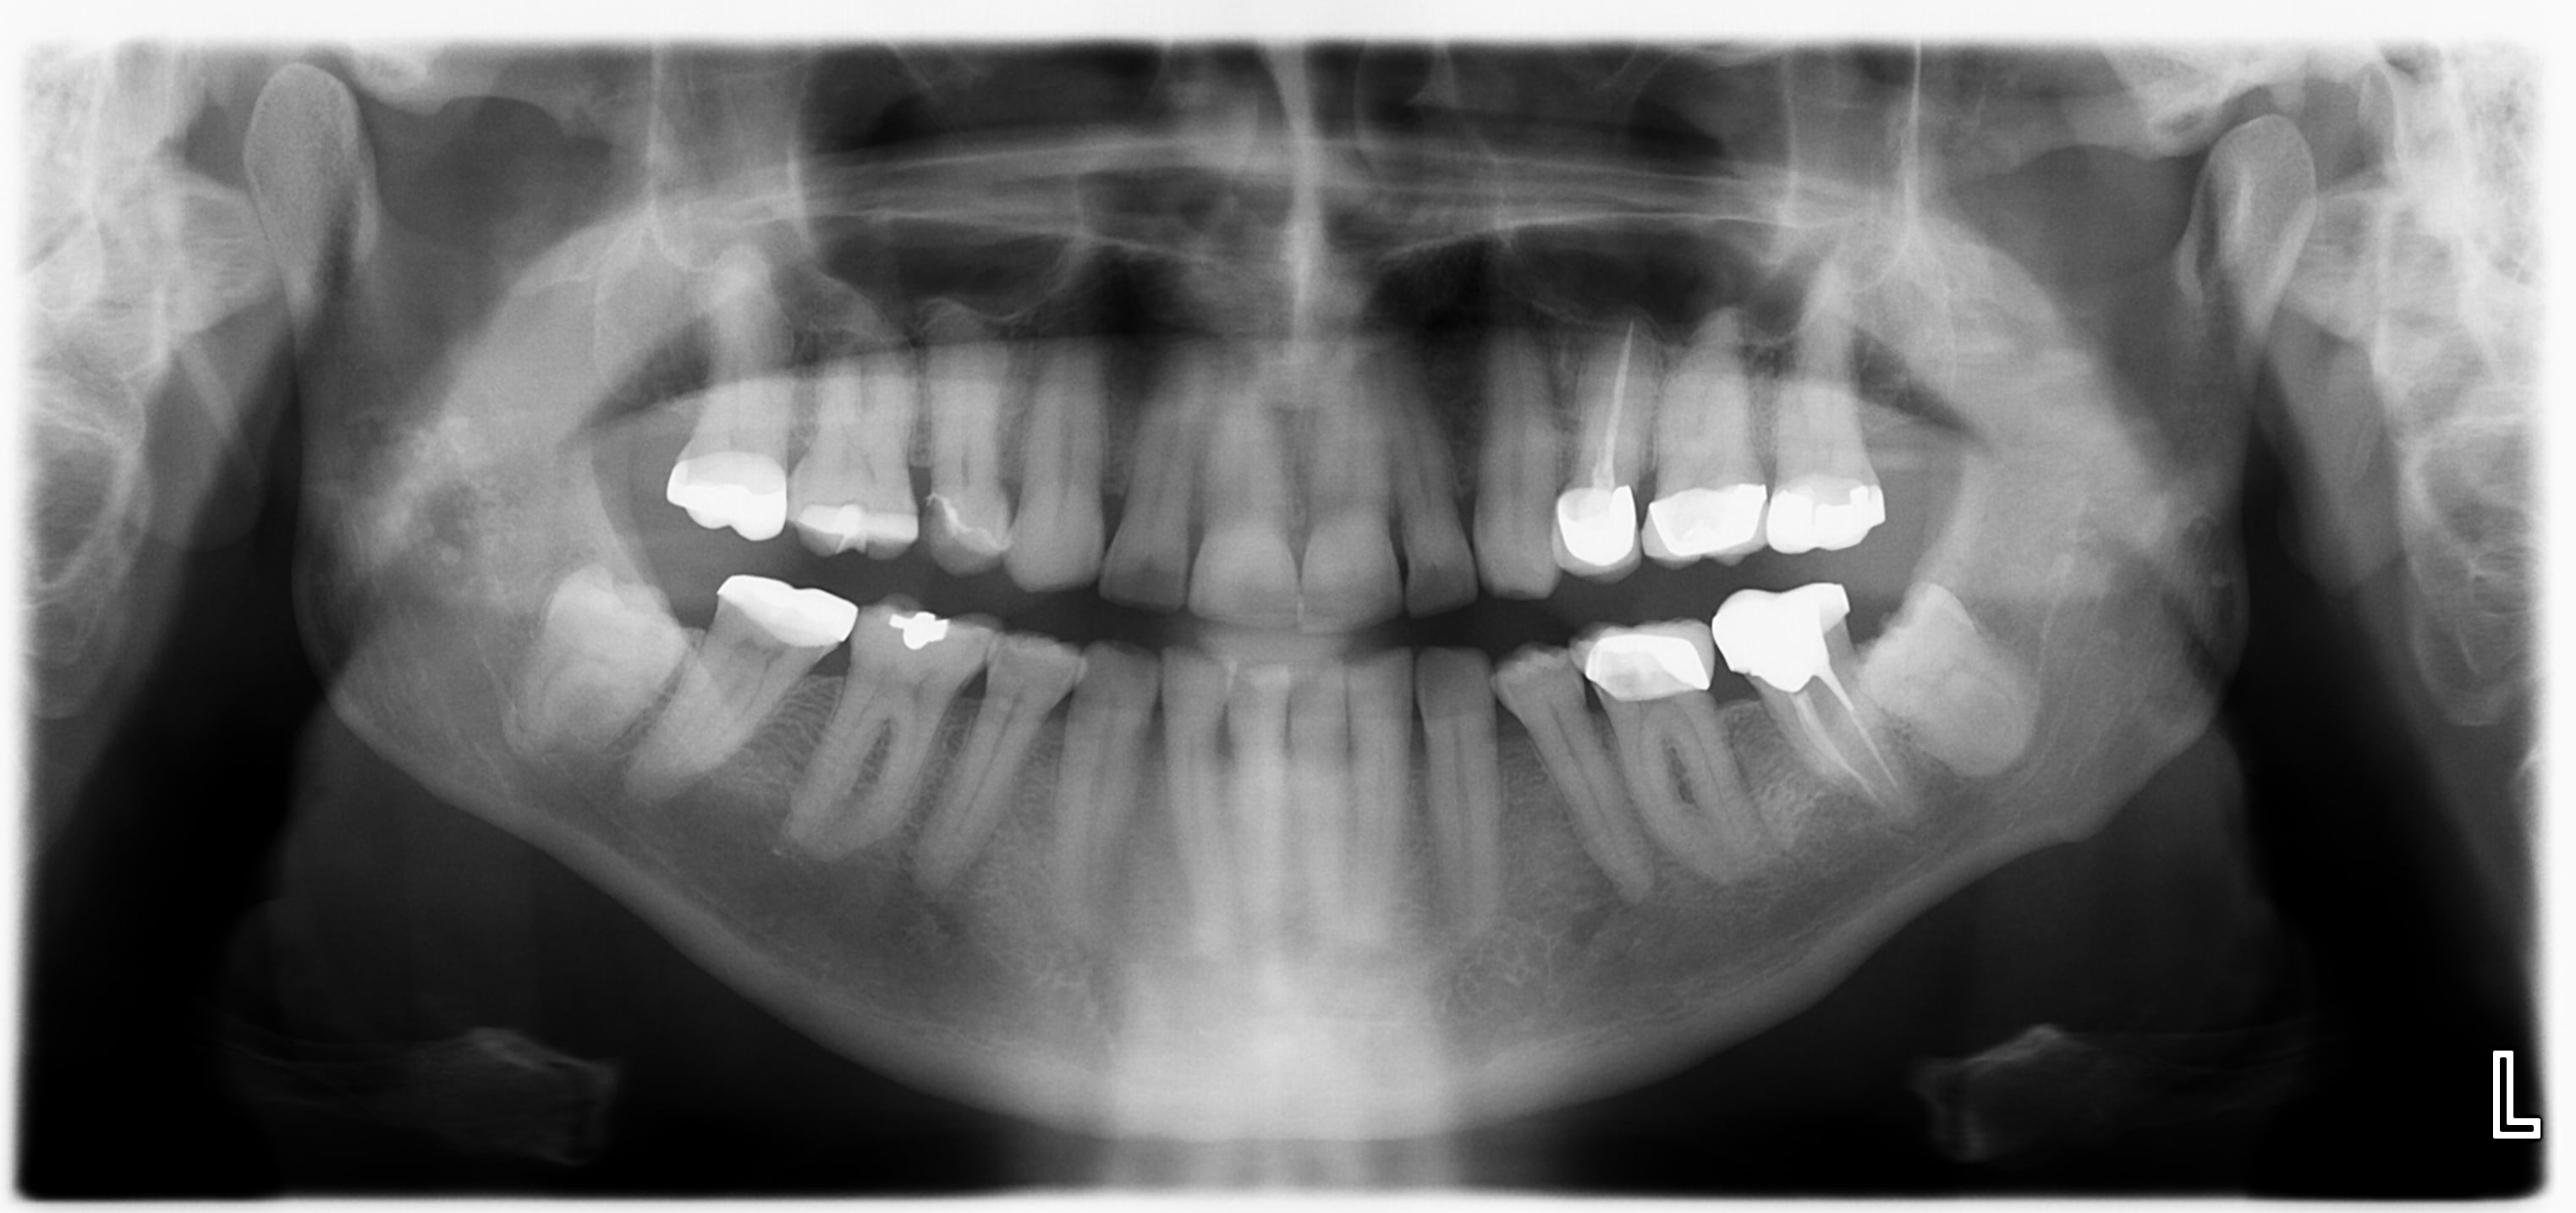

-la première, patient de 60 ans, santé RAS, non fumeur. Pour moi, lithiases de la glande parotide, abstention et je n'envoie pas. Un autre avis?

Le 1 je vois pas grand chose mais si tu penses à une lithiase il y’a des symptômes ? Sinon adresse en cas de doute vaut mieux adresser pour rien que l’invérse.

Pour la première, je pense que je tenterais avant tout palpation jugale et un cliché classique en mettant le film en "vestibulaire" de la mandibule et en essayant de chopper la parotide à la radio pour confirmer que ça vient bien de là. L'option CBCT s'envisage également.